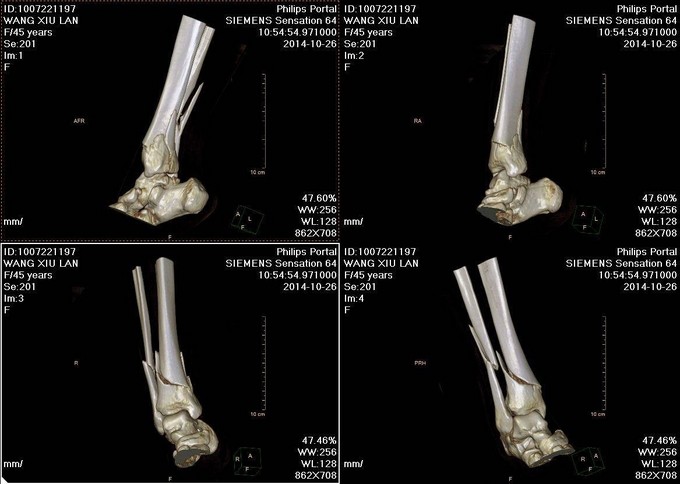

主诉:右小腿外伤后6天 现病史:患者2014-10-19日晚9时左右下楼时不慎摔倒,后于骨科医院就诊,行右下肢DR检查,提示右胫腓骨远端粉碎性骨折,后患者于骨科医院行夹板固定,并与当地祝家镇诊所输液治疗,具体治疗方案不详。后患者为求进一步诊治逐来我院。并以右胫腓骨远端粉碎性骨折收入院。患者病来一般状态可,二便正常,饮食睡眠可。

诊断:右胫腓骨远端粉碎性骨折 患者为右plion骨折,入院后局部肿胀明显,给予患肢抬高,冷敷,消肿等对症治疗,密切观察患肢皮肤情况,带皮肤条件良好的情况下,约2周后行右三踝骨折切开复位钢板内固定术。